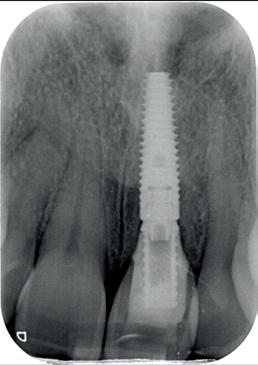

In deze casus is extractie van de 37 geïndiceerd in verband met een fistel en restpockets, zoals zichtbaar op de röntgenfoto’s (afbeelding 1). Duidelijk te zien is de forse peri-apicale ontsteking en het botverlies bij de 37, dat zowel richting buccaal als linguaal doorloopt. De 37 wordt atraumatisch verwijderd. Er is aan de linguale zijde veel bot verloren en er is sprake van een perforatie aan de buccale zijde.

Er wordt besloten om botmateriaal te plaatsen in de extractie-alveole. Vervolgens wordt het afgesloten met een titanium versterkt d-PTFE membraan (afbeelding 2). Na vier weken wordt het membraan verwijderd.

Zes maanden na extractie wordt het implantaat 37 geplaatst. Er is sprake van een goede genezing en de processushoogte en -breedte zijn behouden en opgebouwd. Ook is er zichtbaar gekeratiniseerd weefsel

gewonnen. De wond kan na het plaatsen van een healing abutment primair gesloten worden (Afbeelding 3a-3d).

In afbeeldingen 4a-c is het resultaat drie maanden na het plaatsen van het implantaat te zien. De genezing is volledig en de verwijzer kan de suprastructuur vervaardigen (afbeelding 4a-4c).

In afbeeldingen 5a-d is de implantaatkroon 37 te zien, twee jaar na plaatsing. Op de röntgenfoto is herstel van zowel corticaal als spongieus bot te zien. (De CB-CT was vervaardigd in verband met implantologische indicatie in het naastliggende gebied).

Deze casus illustreert dat er op een voorspelbare manier een ridge preservation procedure uitgevoerd kan worden met een d-PTFE membraan en er daarna voorspelbaar geïmplanteerd kan worden.